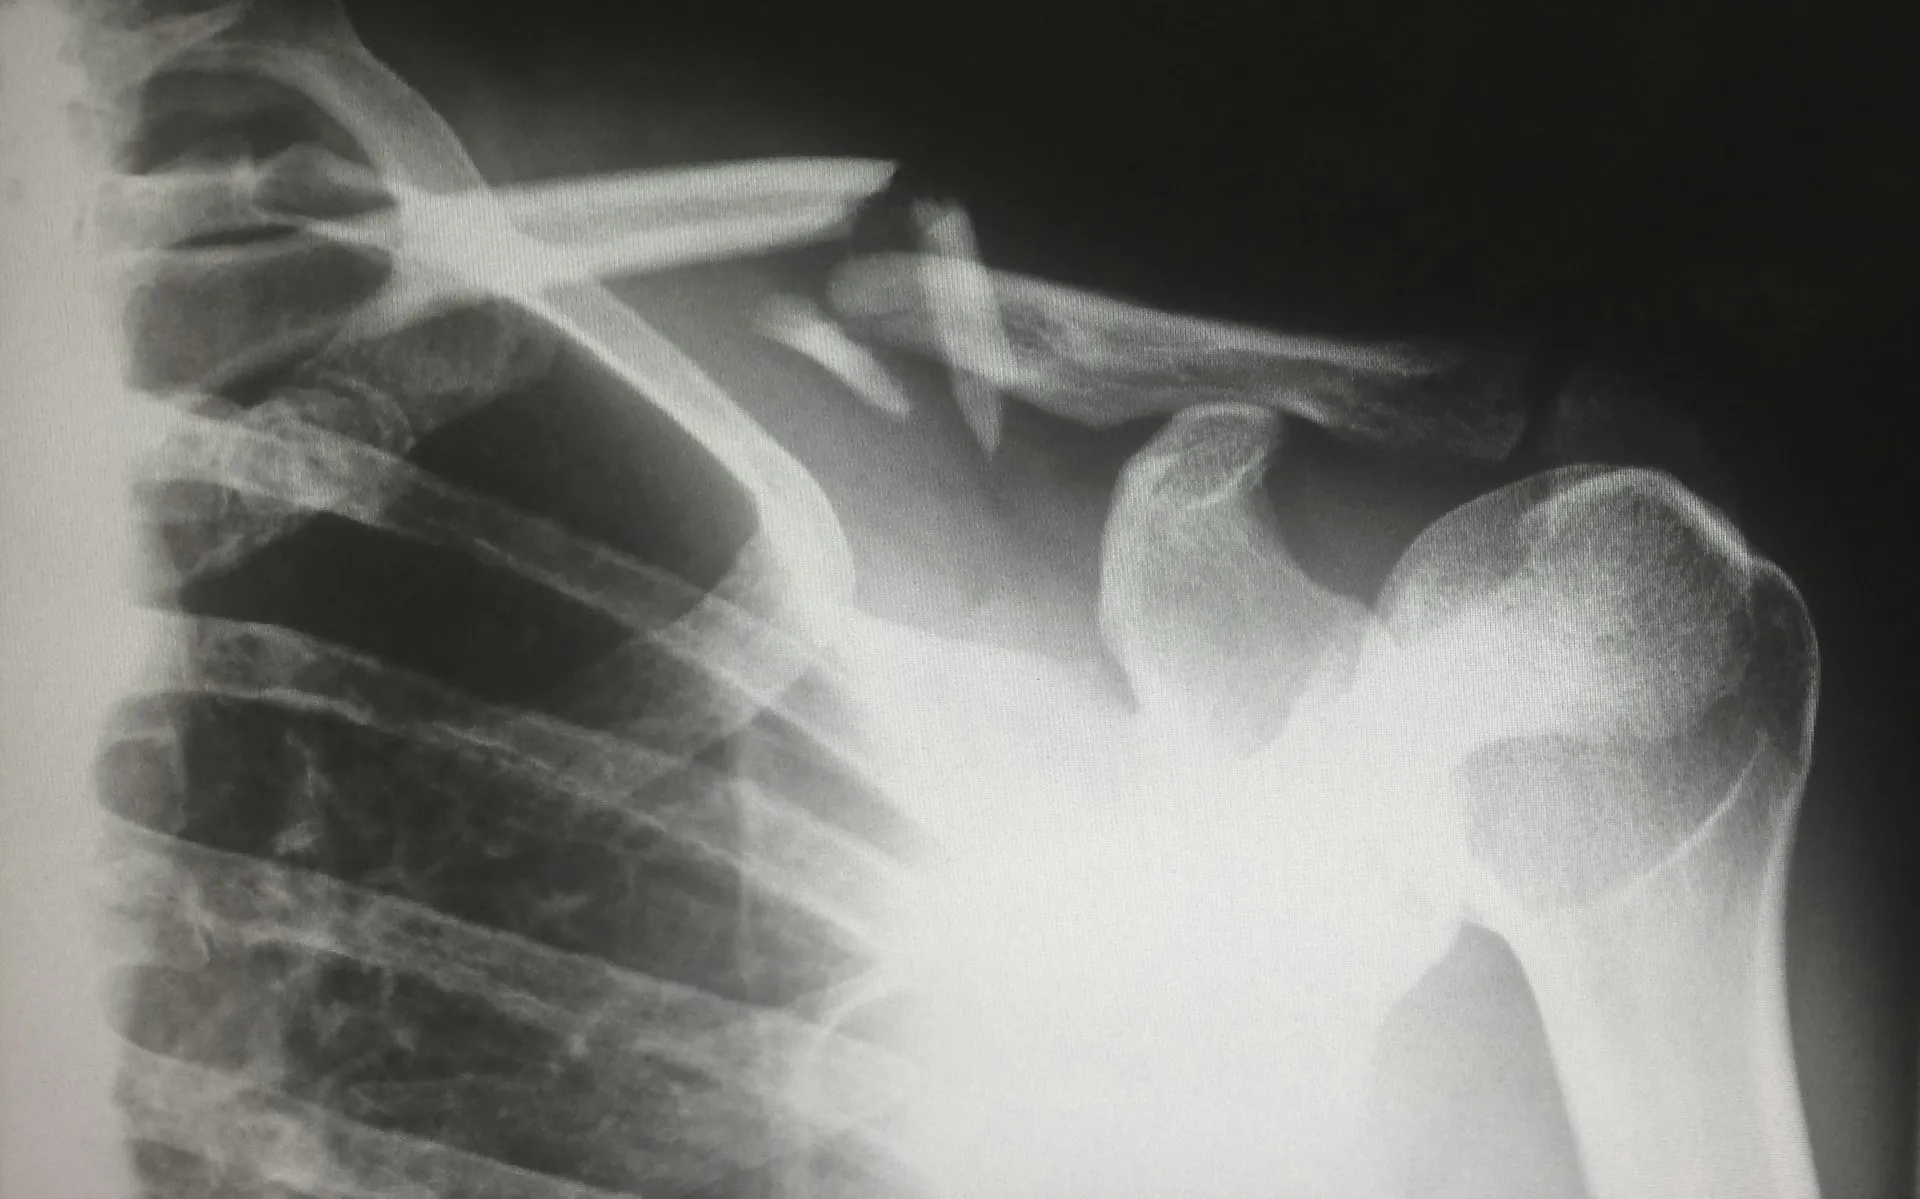

В работе травматологических больниц большую роль играет время года. Например, зимой в гололед увеличивается рост переломов предплечья, а летом с полным комплектом травм обращаются мотоциклисты и любители самокатных гонок.

Некоторые высказывают недовольство по поводу длительности ношения гипса и иногда позволяют себе снимать его раньше времени. На это ортопед отвечает, что сейчас используется преимущественно оперирование. Дело в том, что гипс действительно неудобен для остальных суставов, они обездвижены. Поэтому врачи стараются пользоваться металлофиксаторами.

Одним из самых волнующих вопросов является повторный перелом в случае неправильного срастания. Врач успокаивает, что такая методика осталась в прошлом. За лечением тщательно следят, а если подобная ситуация все-таки произошла, то специалисты проводят реконструкцию под наркозом.